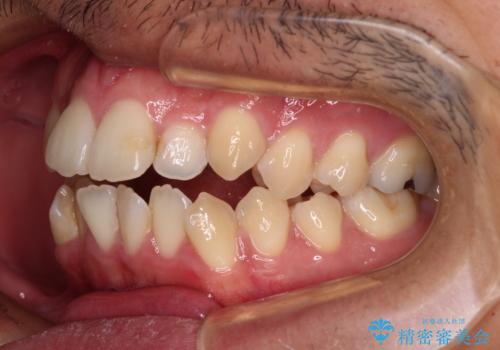

開咬とデコボコを整える インビザライン矯正治療

- 前歯の開咬と叢生を気にして来院された患者様です。

開咬の治療は、前歯を閉じるように動かすとともに、上下臼歯を圧下(骨内にめり込ませる)させることで進めて行きます。

インビザラインは臼歯の圧下を効果的に行えるため、インビザラインを用いて矯正治療を行うこととしました。また、アンカースクリューを用いて、口元の突出感の改善を図りました。